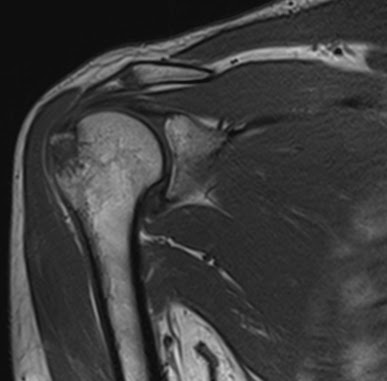

The majority (more than 95%) are either nondisplaced or minimally displaced and can be treated without surgery. The cortical bone of the left greater tuberosity is avulsed at the attachment of the supraspinatus tendon with underlying altered bone marrow signal being of low t1 and high t2 / pd.

Supraspinatus tendon articular surface partial thickness tear. Contrary to proximal humerus fractures, the typical patient who sustains this type of injury is a male, younger. Greater tuberosity fracture clinical evaluation.

5.6cm between top of humeral head and superior edge of tendon.

The greater tuberosity, located on the humerus next to the head of the humerus and the lesser tuberosity, is a large, bulbous protrusion from this i had a skiing accident falling face first at about 25 mph. #fractureofgreatertuberosity#physiotherapyfracture of greater tubrosityintroductionmechanism of injuryclinical features treatmentphysiotherapy treatment#. Who gets them and when do they occur? This type of fracture can interfere with the rotator cuff. Left humeral greater tuberosity avulsion fracture. Swelling and ecchymosis in shoulder which can expend into chest wall and down arm. The authors describe arthroscopic reduction and percutaneous fixation of greater tuberosity fractures of the humerus with displacement of more than 0.5 cm. The subacromial bursa gets pinched between the greater tuberosity of the humerus and the acromion, leading to inflammation and edema. Our data contradict the theory that this. Conquest you have sustained a fracture of your greater tuberosity of your shoulder. This type of fracture can interfere with the rotator cuff. Contrary to proximal humerus fractures, the typical patient who sustains this type of injury is a male, younger. Answer | fractures of greater tuberosity can occur in isolation or in combination with anterior dislocation of the shoulder. There is a weekly thread stickied to the top of the subreddit for these types of submissions. The cortical bone of the left greater tuberosity is avulsed at the attachment of the supraspinatus tendon with underlying altered bone marrow signal being of low t1 and high t2 / pd. The majority (more than 95%) are either nondisplaced or minimally displaced and can be treated without surgery. The impact onto the outstretched arms caused a greater tuberosity fracture of left humerus.